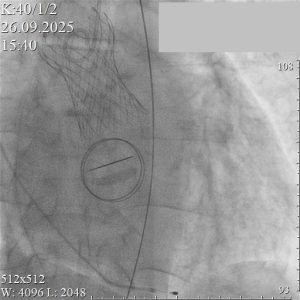

26 сентября 2025 года в Кардиососудистом центре Республиканской больницы №1 – Национального центра медицины имени М.Е. Николаева в третий раз успешно выполнена транскатетерная имплантация аортального клапана (TAVI). Это событие знаменует собой уверенное становление в Республике Саха (Якутия) высокотехнологичного направления кардиологии, позволяющего спасать жизни пациентов с минимальным вмешательством. Развитие этой сложной методики стало возможным благодаря слаженной работе и целенаправленной поддержке руководства Национального центра медицины.

TAVI – это современная малоинвазивная процедура, которая кардинально меняет подход к лечению пороков сердца. В отличие от традиционной открытой операции, замена клапана проводится без единого разреза на грудной клетке. Хирурги выполняют все манипуляции через тонкий катетер, проведенный к сердцу по кровеносному сосуду. Ключевые преимущества метода –значительное снижение травматичности, минимальный риск осложнений и короткий период восстановления.

Вся процедура заняла около двух часов. После операции пациент был переведен в палату реанимации для наблюдения, а уже через сутки – в общую палату, где продолжил восстановление без существенных ограничений.